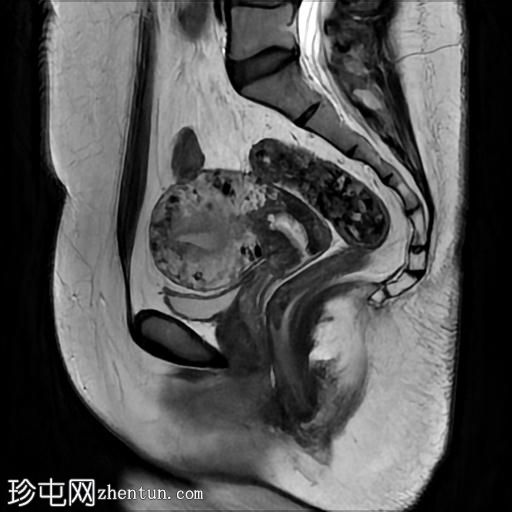

轴位T2加权像

脂肪抑制像

盆腔MRI显示双侧子宫旁多条迂曲静脉,自子宫肌层延伸至盆腔。

此外,左侧附件可见两个充满液体的单纯性囊肿,大小分别约为31 mm和32 mm;右侧附件可见一个卵泡囊肿,大小约为19 mm。

影像学特征符合盆腔充血综合征的诊断,患者为35岁女性,有慢性盆腔疼痛和痛经病史。